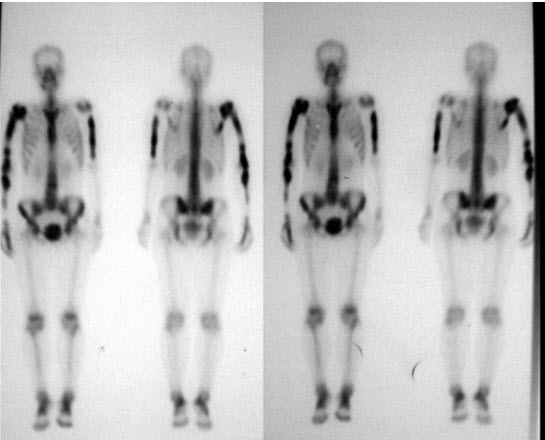

40、单项选择题

男,32岁,双侧上肢疼痛3个月,有慢性肾炎病史,无发热、无外伤及肿瘤病史,行全身骨显像如图,最可能的诊断是()

A.骨纤维结构不良

B.肾性骨营养不良

C.Paget病

D.双侧上肢骨转移癌

E.以上都不是